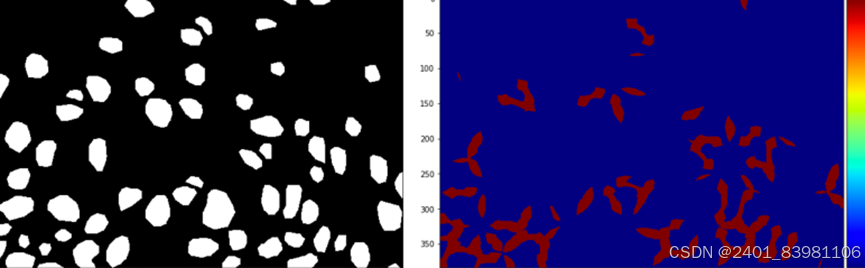

单独应用深度学习网络SBDL来提取和识别舌头裂缝 ,如图:

形质识别:现状:特殊如齿痕,腐腻等不能全面分析。针对齿痕、裂 纹等单一形质特征的研究较深入:

3. **纹理特征**:

- 灰度共生矩阵(GLCM):提取纹理信息的统计特征。

- 局部二值模式(LBP):描述局部纹理结构。